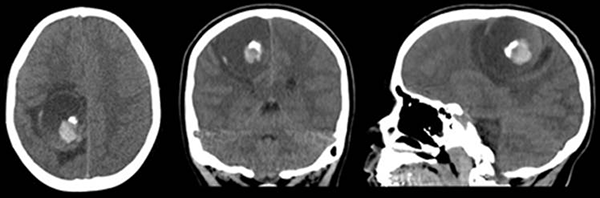

Se presenta un paciente femenino de 10 años que ingresa a nuestro hospital por presentar hemiparesia braquiocrural izquierda, vómitos y cefalea de 72 horas de evolución. Se constatan ambas papilas opticas sobreelevadas en el fondo de ojos. Se decide realizar tomografia computada (TC) (fig. 1) y resonania magnética nuclear (RMN) de encéfalo (fig. 2).

Figura 1: TC. A) corte axial; B) corte coronal; C) corte sagital. Lesión expansiva esferoidea, sólido-quística que contiene una foración endofitica de densidad heterogénea, ubicada en la región fronto-parietal derecha. Se observa halo hipodenso perilesional, compresión del cuerpo del ventrículo lateral derecho y del cuerpo calloso, con ligero deslazamiento de la línea media.

En cuanto al diagnóstico, puede realizarse a partir de muestras de LCR o tejido cerebral por observación microscópica directa o previo cultivo en agar no nutritivo cubierto por una capa de E. coli o Enterobacter aerogenes en crecimiento exponencial a 25 ºC.No es habitual la obtención de una muestra de LCR, ya que que con frecuencia los pacientes se presentan con síndrome de hipertensión endocraneana en cuyo caso la realización de una punción lumbar se convierte en un procedimiento riesgoso. El estudio anatomopatológico del tejido cerebral permite observar, como rasgo más característico, la formación de granulomas en hospedadores inmunocompetentes (en hospedadores inmumocomprometidos estos estan habitualmente ausentes) y trofozoítos invadiendo las paredes de los vasos sanguíneos y rodeados de abundante cantidad de células inflamatorias.2,3,6,10 En cuanto a las neuroimágenes obtenidas, ya sea por TC o por RMN, las lesiones muestran predilección topográfica por el compartimiento supratentorial, ubicándose más habitualmente en los lóbulos frontal, parietal y temporal, pudiendo ser unifocales o multifocales, unilaterales o biltaterales, con edema y efecto de masa perilesional variable. Características que hacen a estas lesiones muy variables y sugestivas de otras patologías como tumores o abscesos piógenos.2,4,5